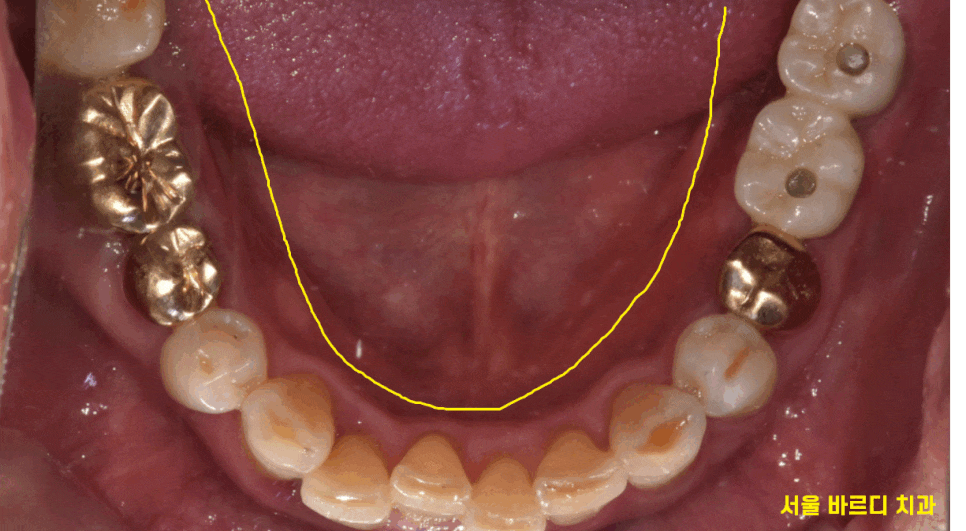

240610

3차원적 관계를 ct를 통해 확인이 가능합니다.

앞, 뒤, 좌, 우, 옆

360도 돌려가며 파악이 가능합니다.